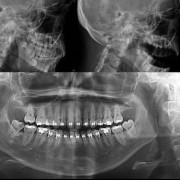

- Exposiciones teóricas por grupos de patologías con aplicabilidad práctica: cuando el caso lo requiera se realizará una demostración de cómo se puede solventar un problema: suturas, anestesia local, ferulización dental. Presentación de casos clínicos, que permitirán una mejor comprensión de los conceptos expuestos.Discusión.